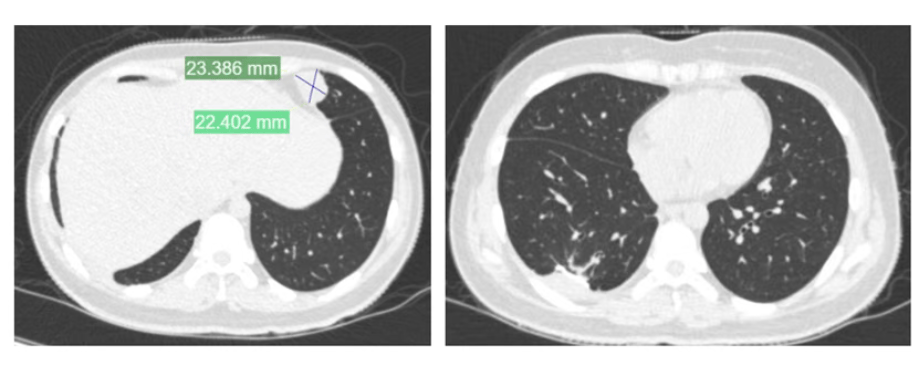

夏夏前期接受了术前化疗、截肢手术及术后化疗,使用的是一线化疗方案皇冠信用盘代理 。然而,结疗不到一年,肺部出现转移病灶,经过手术切除后未再进行化疗。术后5个月,左肺再次发现新发转移病灶。

2024年11月,夏夏接受胸腔镜下右肺下叶切除术皇冠信用盘代理 。2025年1月复查:右肺术后改变。

夏夏在最新的视频中表示,癌症转移到胸膜,她去瑞金医院寻求治疗方案,她将在上海接受肋骨和胸膜的切除手术皇冠信用盘代理 。视频中的夏夏虽然有疲态,但依旧乐观,还感谢帮助她推轮椅的好心人。